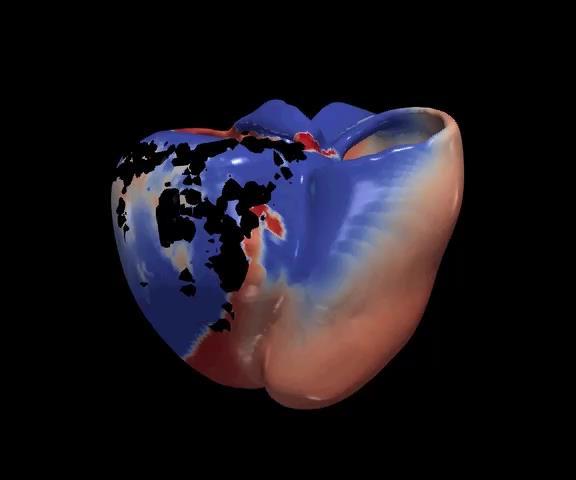

What if we could create a digital twin of the patient’s heart?

• Multiscale, Personalized Physiological Model of the patient’s heart

• Anatomy, Electrophysiology, Biomechanics (muscle contraction ), Circulation (ejection fraction, pressure dynamics)

• Mechanistic and statistical modeling

• Model is under our control

• Potential to test and prescribe best therapy for the patient – e.g., Cardiac Resynchronization Therapy

Ventricular Tachycardia Atrial Fibrillation Dyssynchrony – Heart Failure

Identify the ablation targets that will effectively terminate persistence AF? Identify the minimal ablation targets (catheter, RT) that will effectively terminate VT?

Cardiac radioablation –focus radiation using localization of VT exit

Anticipate the effects of CRT on patient’s cardiac function from preoperative data?